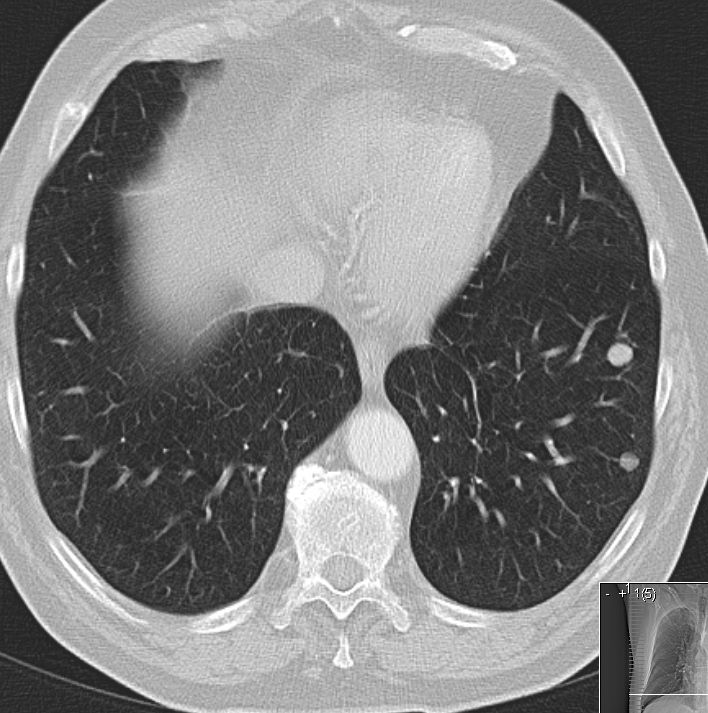

| Lunge | ![]() |

![]() |

![]() | |||||||||||||||||||||||||||||||||||||||||||||||||||||||